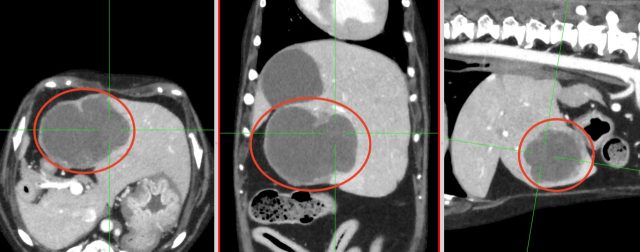

胆管癌のCT画像(赤丸)

・CT検査:がんの大きさや広がり、リンパ節転移、遠隔転移の評価

※CT検査はより綿密な治療方針を決定するうえで必須の検査です